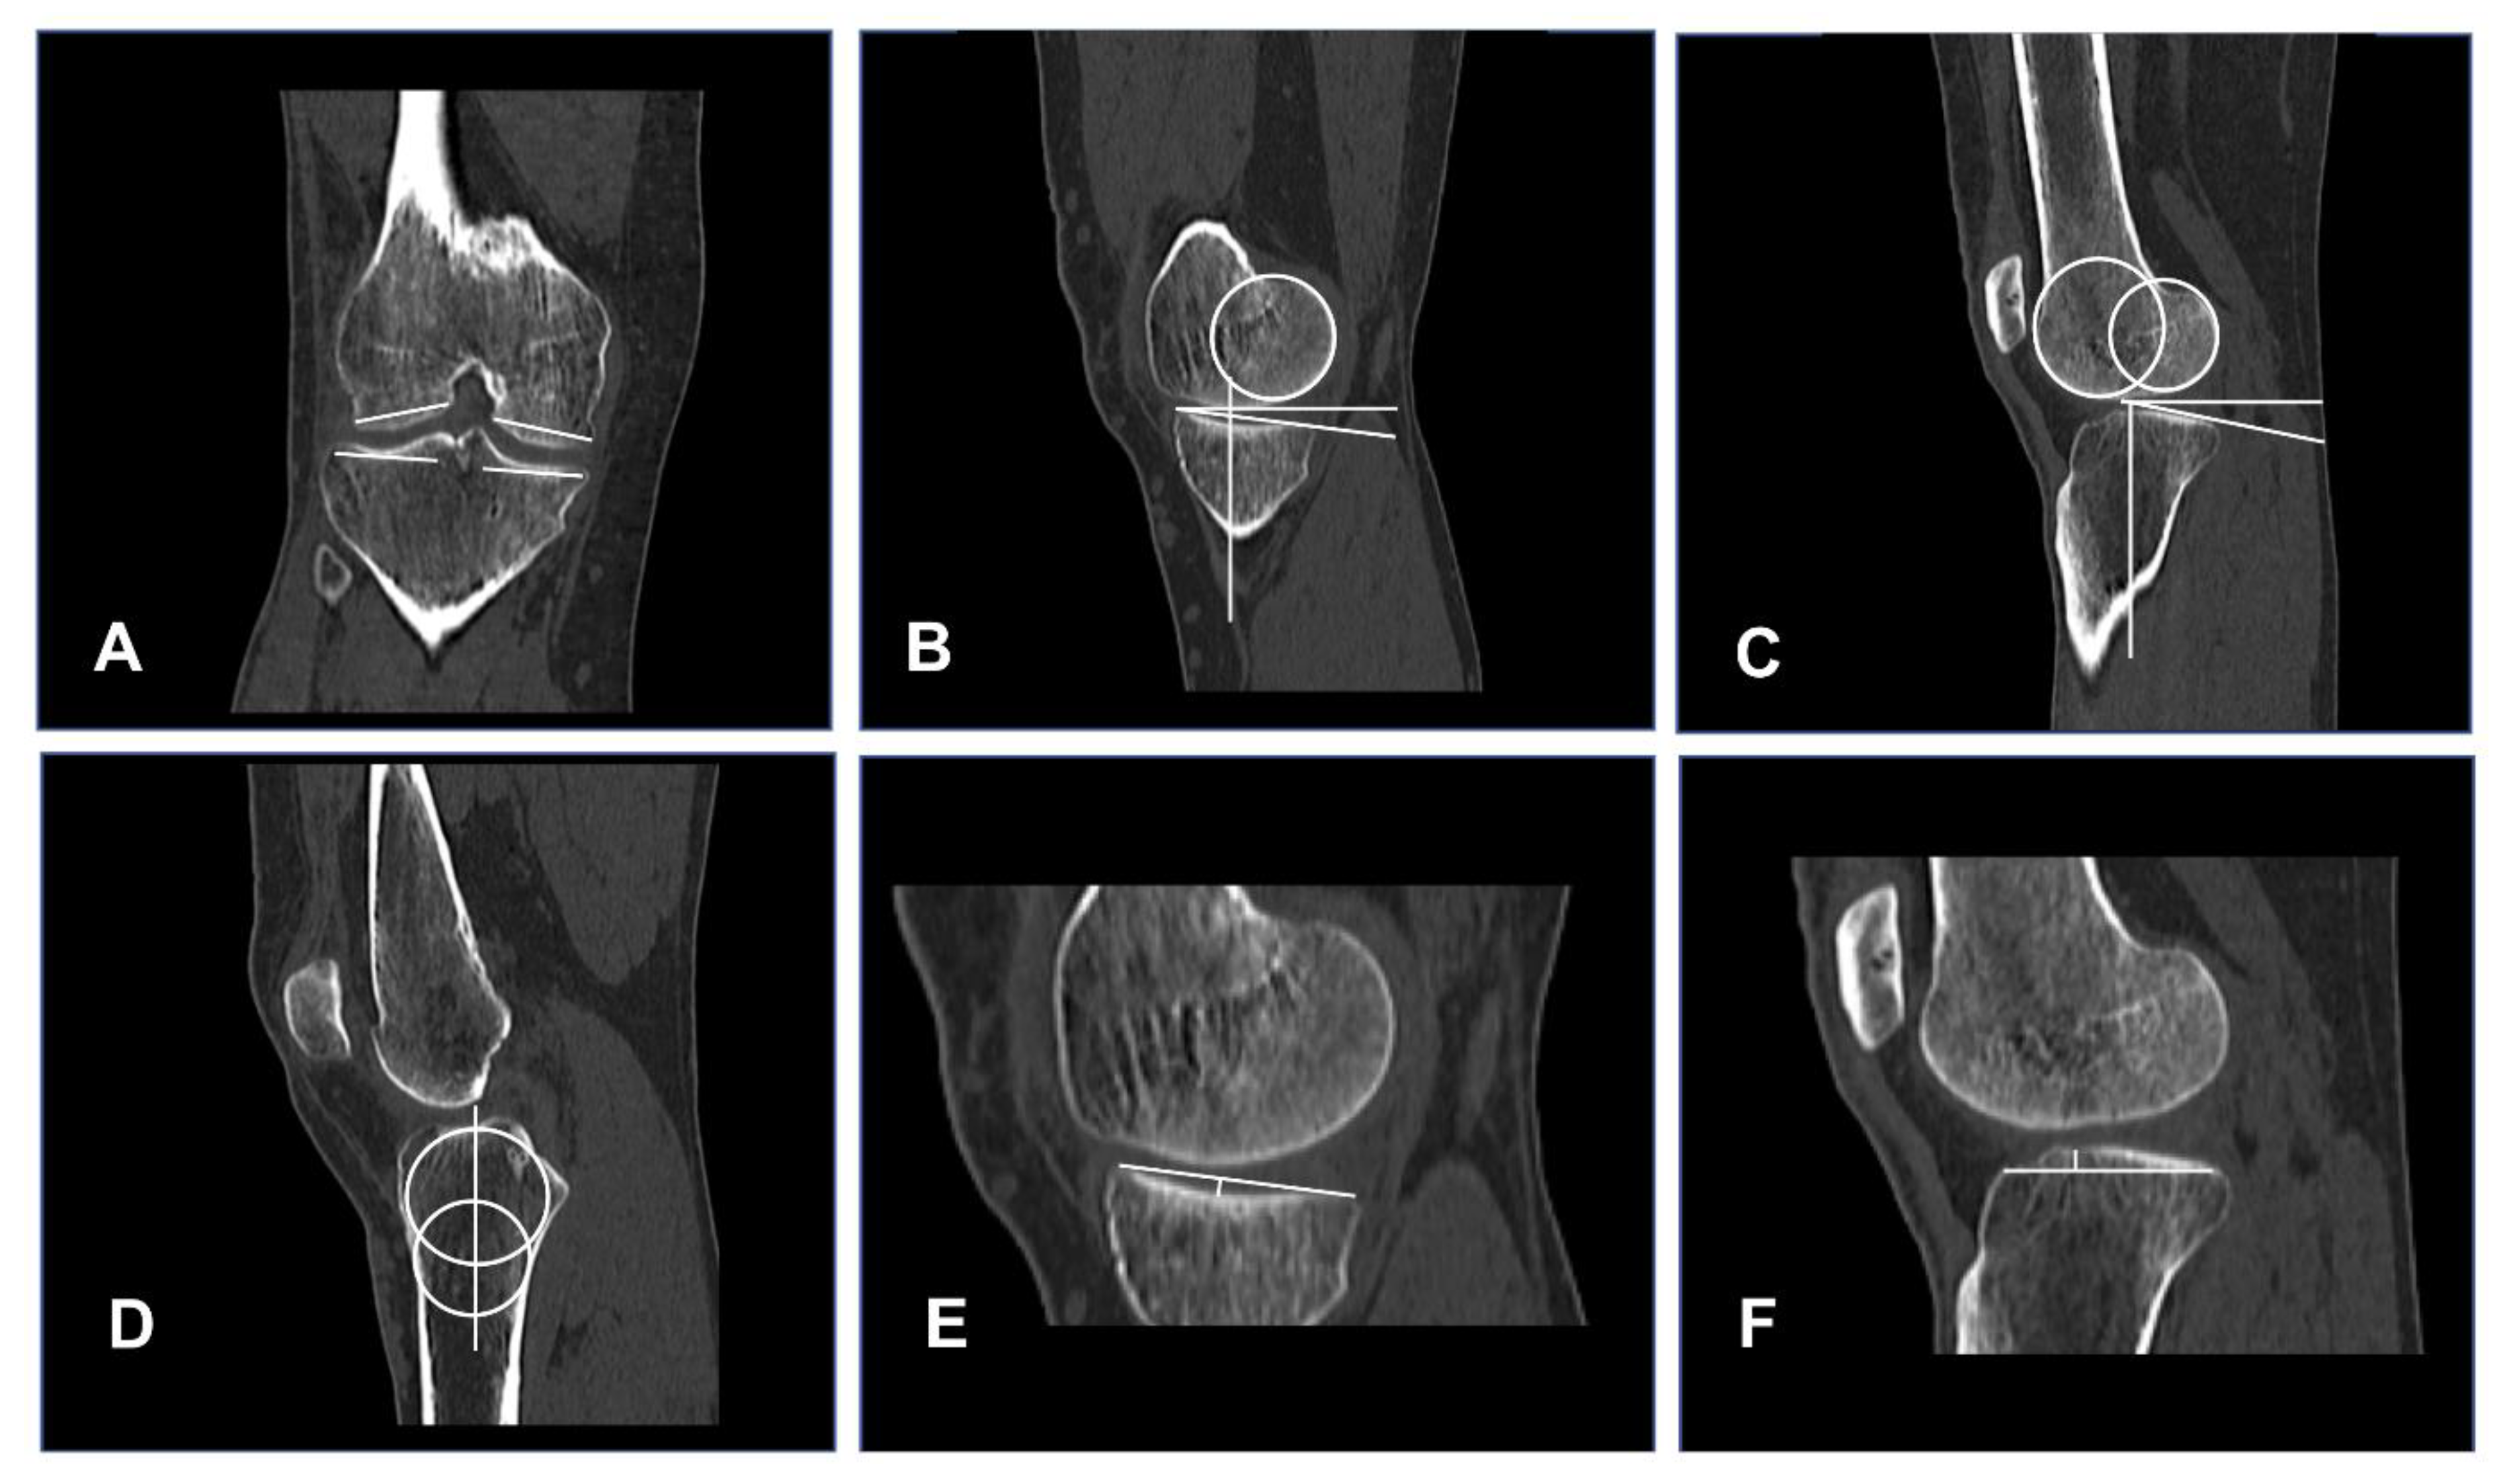

2.2. Femoral and Tibial Bone Morphology

- Femoral bone morphology:

- Tibial bone morphology: